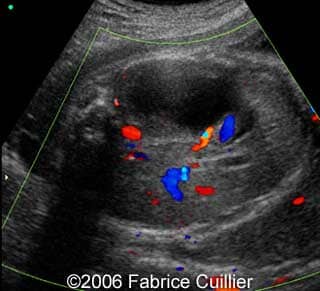

• an abnormal polycystic left kidney (34 X 17 mm) with an abnormal corticomedullar differentiation. This kidney was on the lumbar fossa.

Transverse view of the normal right kidney and the abnormal left kidney